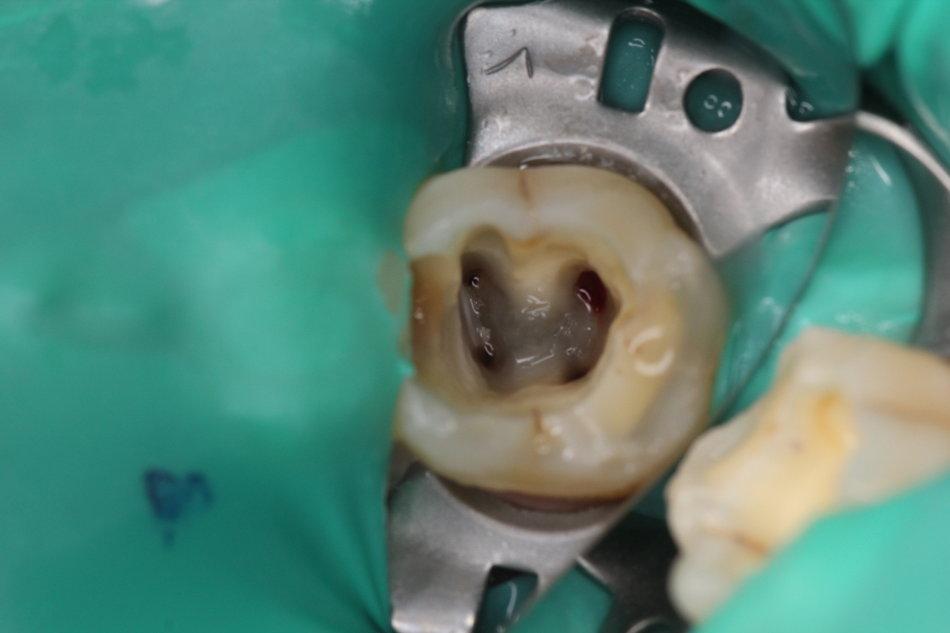

1、一般根管治疗后都是建议要套一个冠。根管治疗后套冠是为了保护失去活力的牙齿,防止牙齿崩裂。